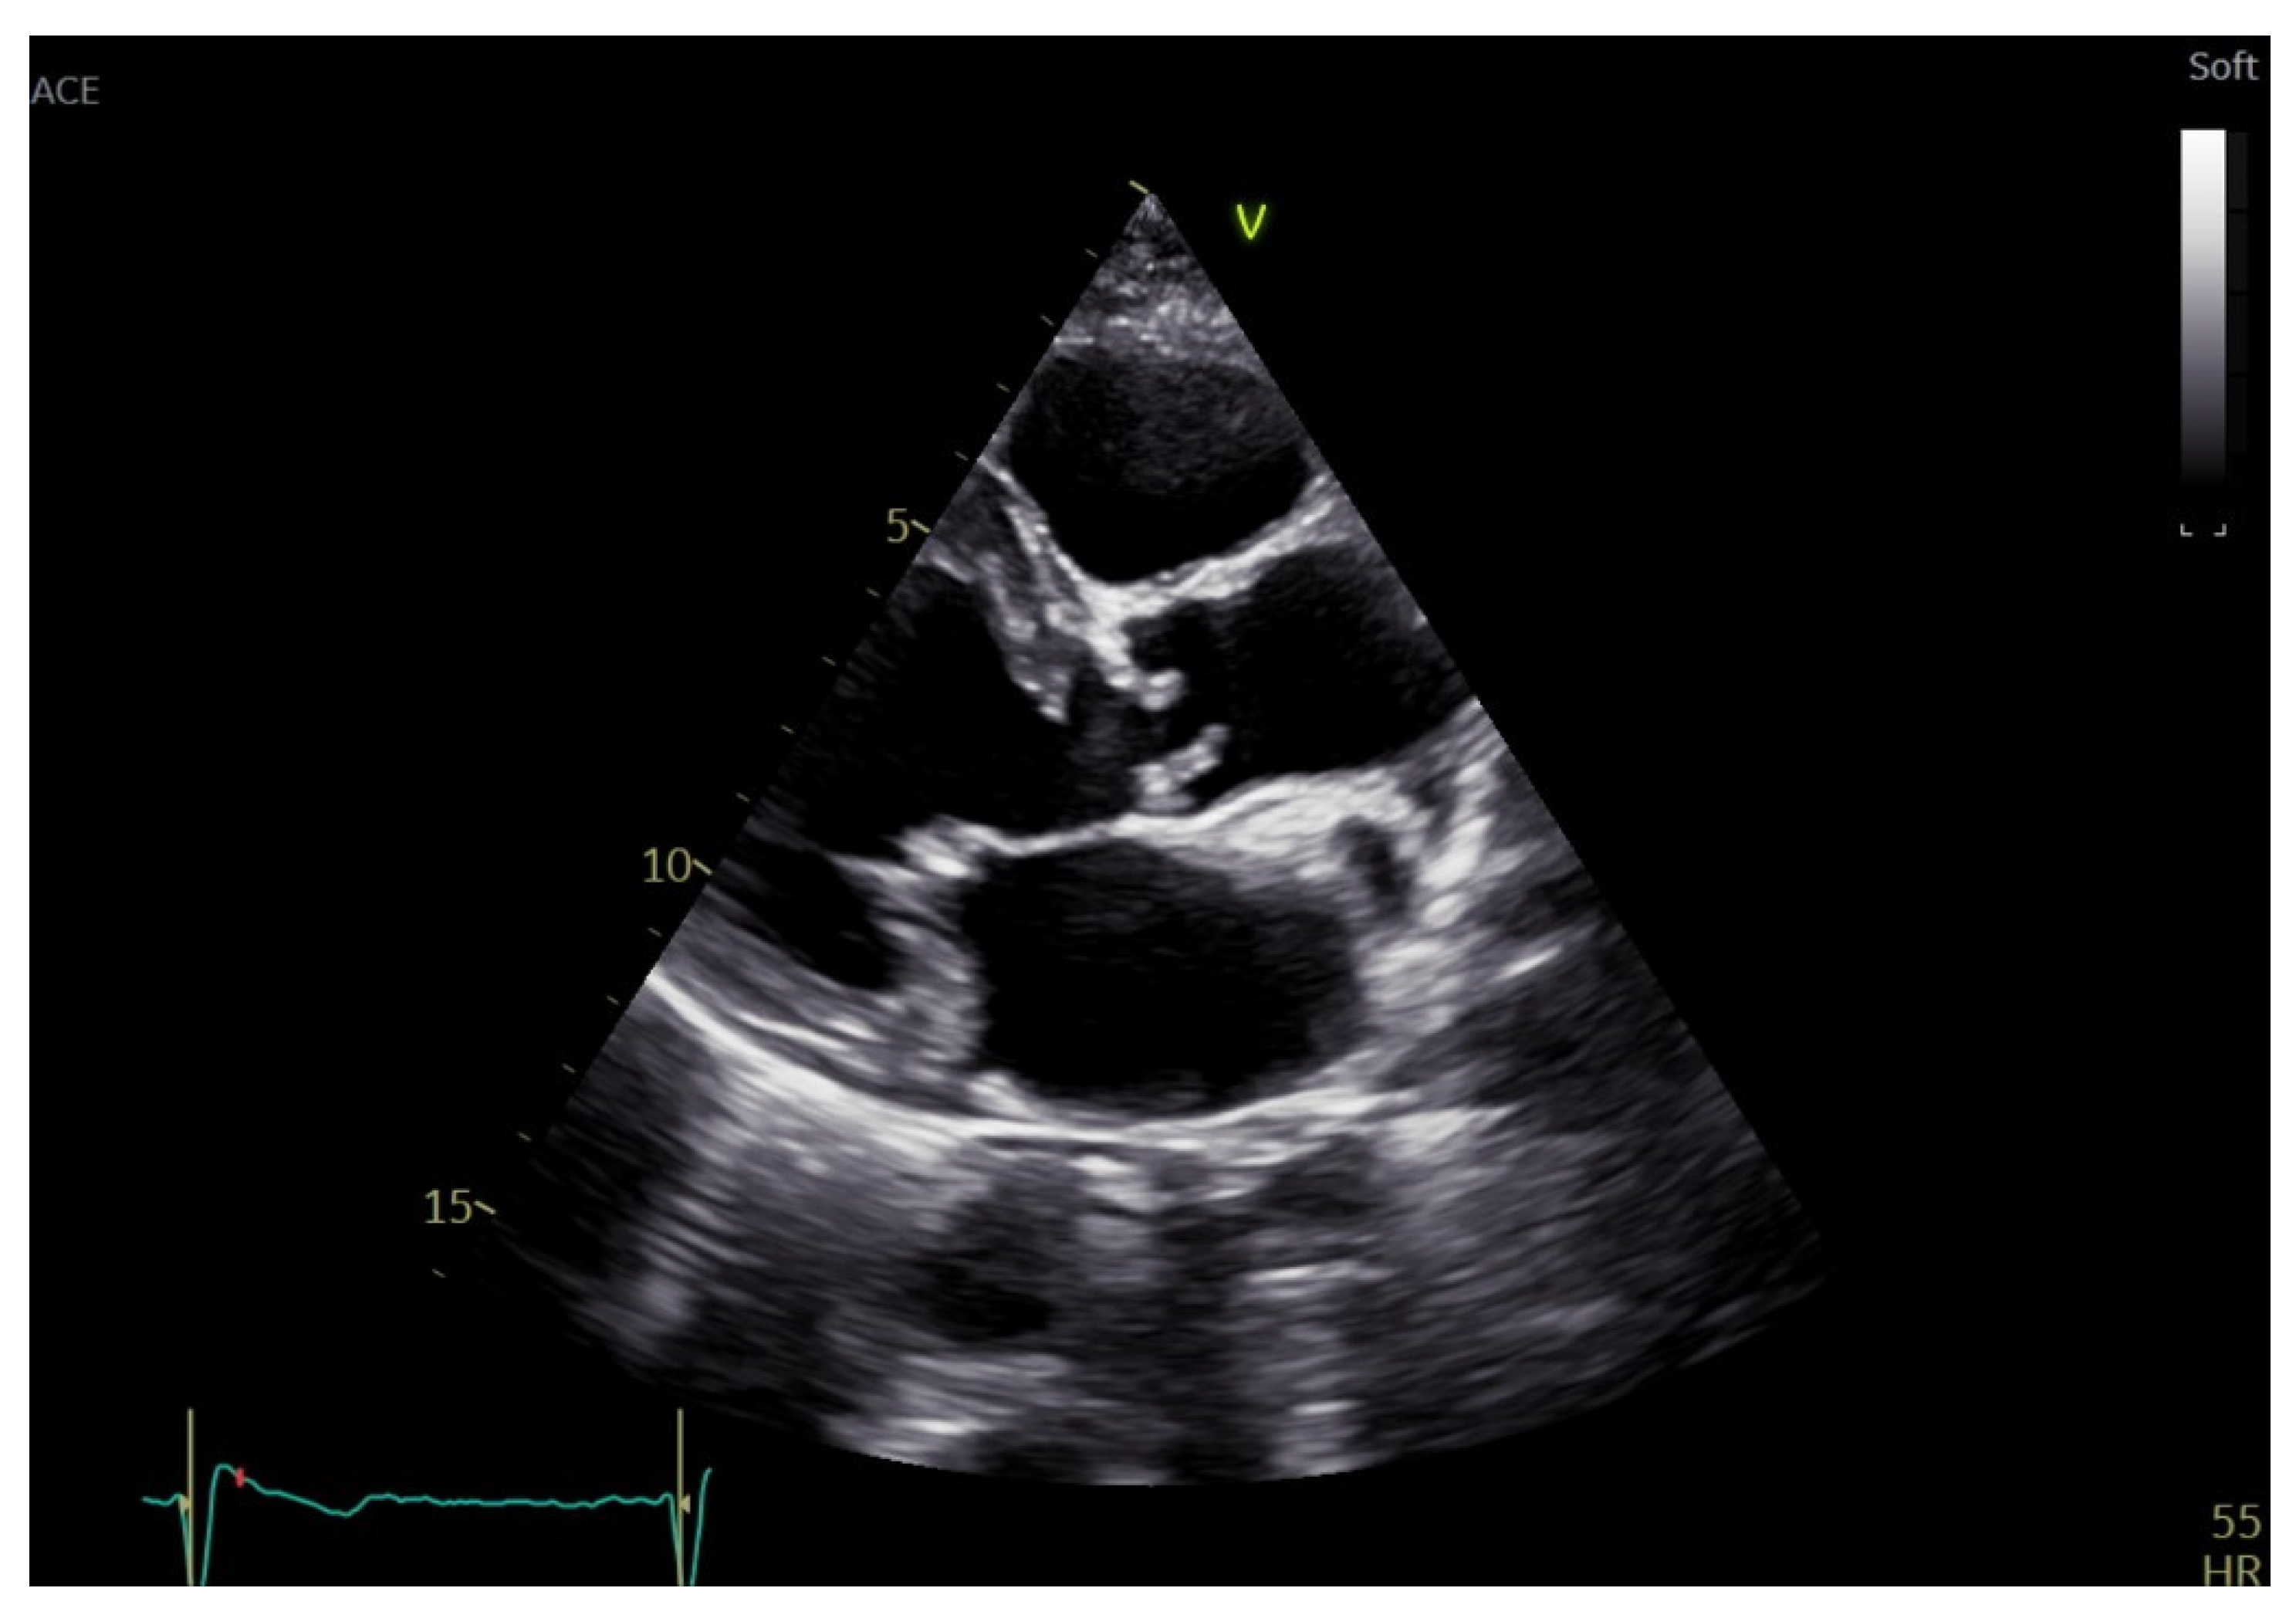

Echocardiographic Evaluation of Aortic Stenosis: A Comprehensive Review

2. Aortic Stenosis Etiology and Echocardiographic Morphologic Assessment